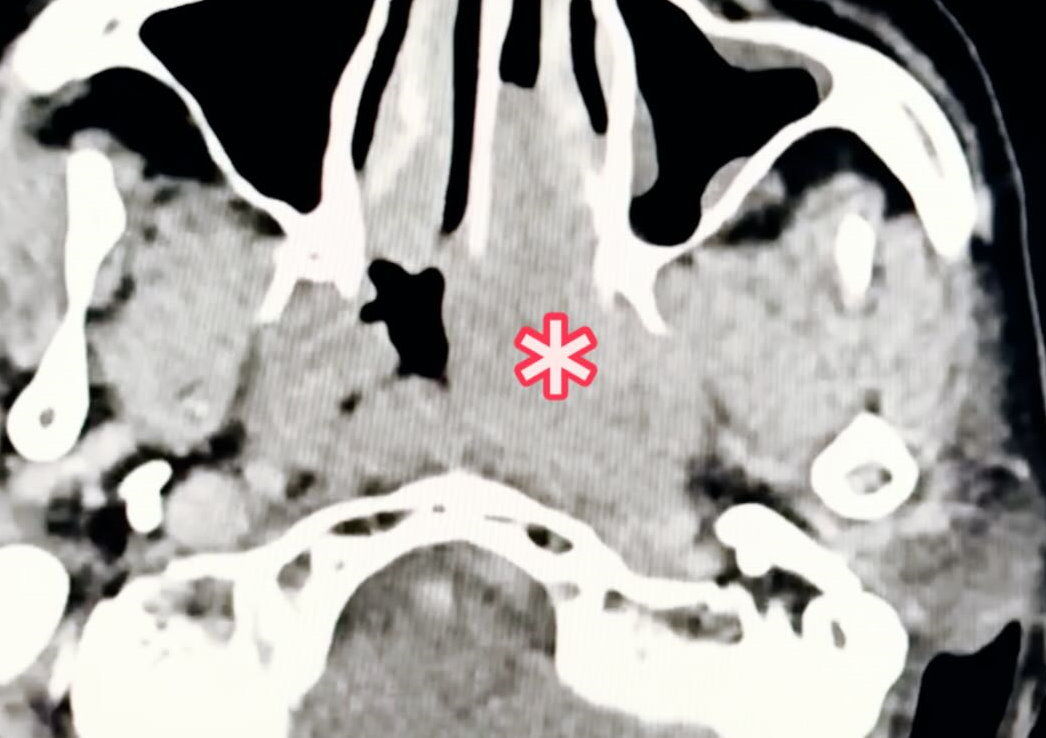

▼患者的鼻咽腫瘤。(圖/翻攝李典憲臉書)

李典憲提到,這必須再用內視鏡檢查鼻咽部的狀況,結果用內視鏡一照,居然看到一個超大的鼻咽腫瘤!當下趕快轉去醫學中心做進一步治療,因腫瘤很大,心想如果是鼻咽癌,這個應該偏晚期,不知道阿姨身體有沒有辦法撐過治療(化療與放療)。